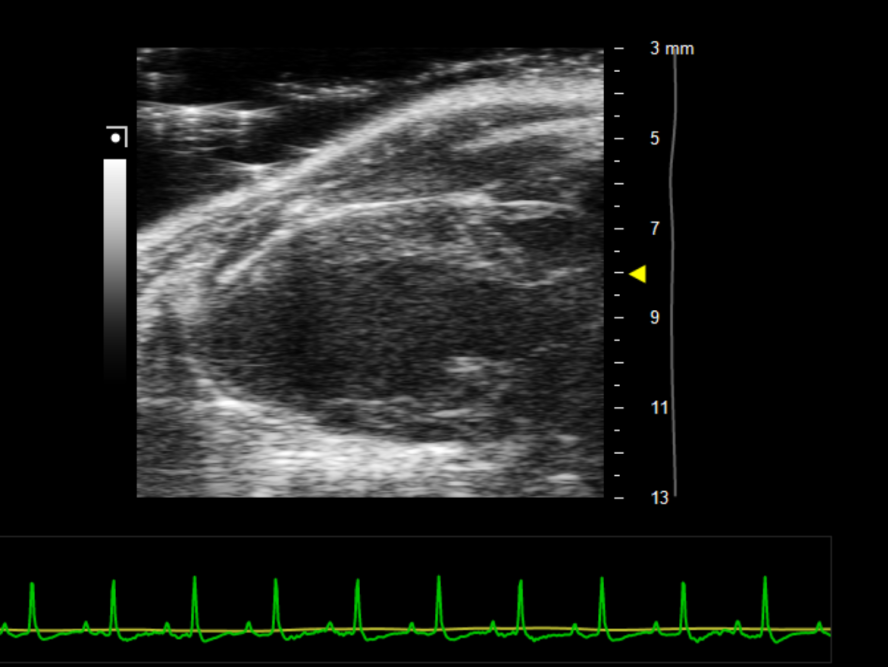

4.胸部区域涂抹耦合剂,平台向左下倾斜30度左右,并将探头放置于小鼠胸部正中间朝向十一点钟方向,如图1所示,可获取左心室胸骨旁长轴切面,定位后可微调操作台X/Y轴至左心室轮廓清晰,左侧为心尖,右侧对应主动脉流出道,需保证心尖与流出道水平。获取画面如图2所示。

图2 左心室胸骨旁长轴(B-Mode)